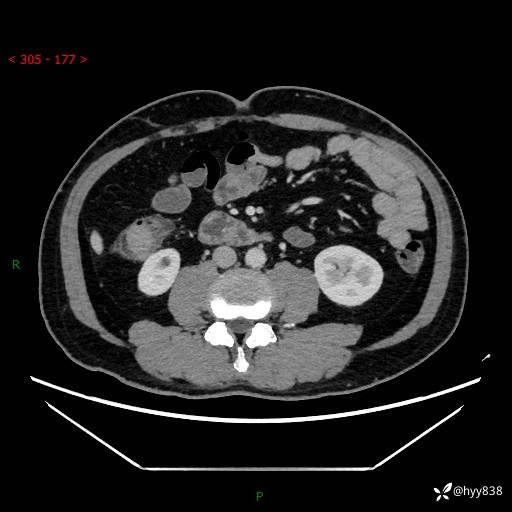

腹部CT增强扫描(外院CT平扫)

两期CT值:75hu 82hu